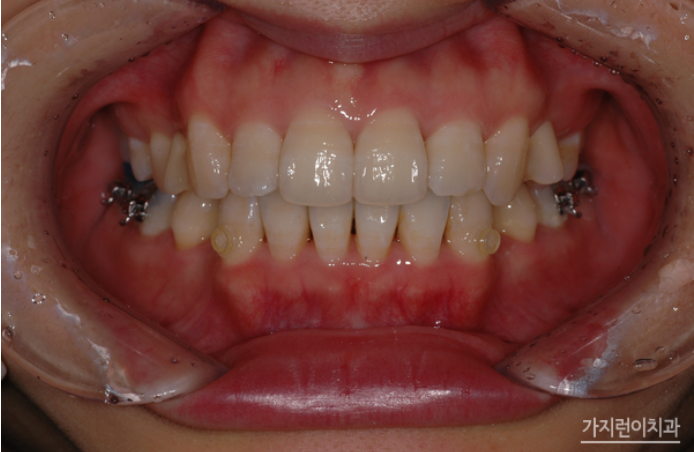

위 사진처럼 설측으로는 복잡해보이는 장치가 보이지만 이를 앙 다문 상태에서는 장치가 보이지 않는데요. 두 개의 와이어를 사용해 치아이동에 필요한 힘을 효과적으로 줄 수 있는데다 치아의 쓰러짐을 방지해 마찰력을 줄여 결과적으로는 치료기간이 크게 단축되었다는 것을 볼 수 있습니다. 게다가 덧니, 돌출입, 비발치 교정 등 기존 설측교정장치보다 빠르고 탁월한 결과를 얻어볼 수 있겠습니다.